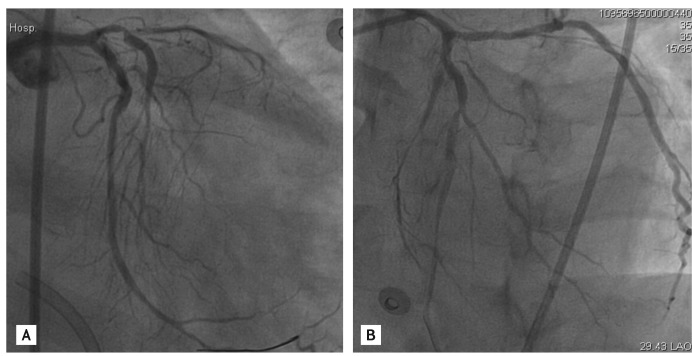

Figure 3

(A) The dislodged stent with guide wire seen in the ascending thoracic aorta. (B) A gooseneck snare (St. Jude Medical) was passed into the guide catheter and the stent was snared successfully. (C) The snared stent together with the guide catheter was removed from the femoral artery sheath.